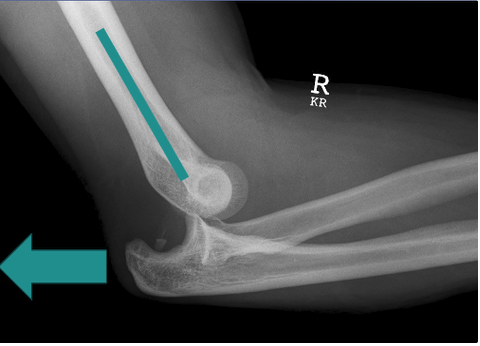

What is shown in the X-ray?

A

Posterior dislocation

What occurs in posterior dislocation of the elbow?

The ulna and radius move posteriorly to the humerus